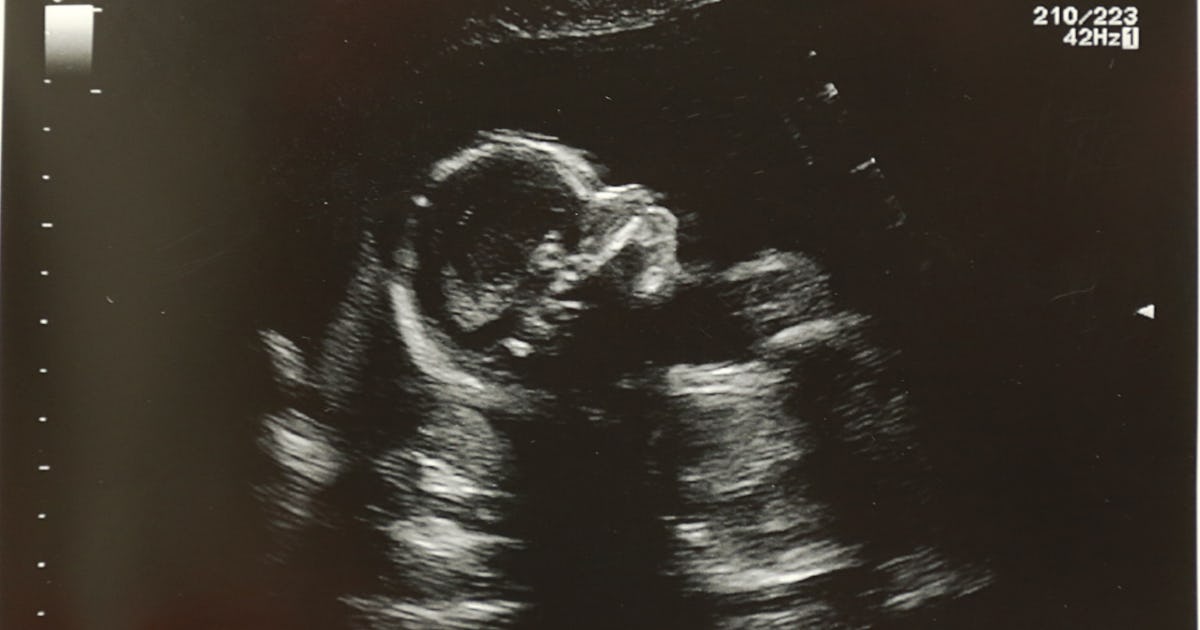

Share on Pinterest Have a nice day PhotoShutterstock A 7-week ultrasound showing crown rump length of baby which helps figure out the age of the fetus. As a Catholic abortion was never an option. Baby also has ear lobes and the very tip of their nose can be seen in profile.

Conversely puppies will usually need to void their bladder within 10 to 30 minutes of filling up their tanks. Doctors typically schedule the structural ultrasound also called the anatomy screen or level 2 ultrasound between week 18 and week 22. Babys body continues to straighten out while the embryonic tail disappears.

Ultrasound Offers Noninvasive Method to Target Drug Delivery in Animal Brain A research team used ultrasound waves to break up a nanoparticle-filled anesthetic to target the visual cortex of a rat brain. This ultrasound checks how your baby is developing the location of the placenta the babys position and the status of the major parts of the brain heart kidneys bladder and stomach. Her exam vital signs and blood work were normal and an ultrasound showed a healthy growing baby.

The ultrasound scan will determine viability your babys heartbeat if single or multiple fetus are present and accurately date your pregnancy. Surrounding the fetus is the gestational. Your words are true and I know that you love me beyond measure.